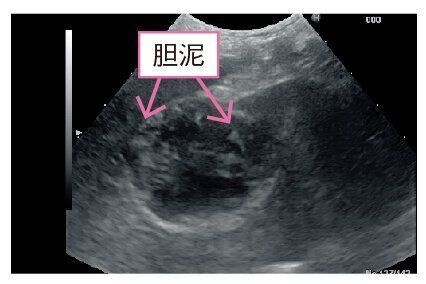

胆嚢粘液嚢腫[たんのうねんえきのうしゅ]

《胆嚢の中に泥状の胆汁がたまる》

胆嚢は肝臓の隣にある臓器で、肝臓の中でつくられた胆汁をためておく働きがあります。この胆汁がなんらかの原因でベトベトした泥状になり、胆嚢の壁に張りつくのが胆嚢粘液嚢腫です。成犬期~シニア犬期で発症し、進行すると嘔吐や黄疸などの症状が見られますが、初期はほぼ無症状で、血液検査だけでは見つけられません。